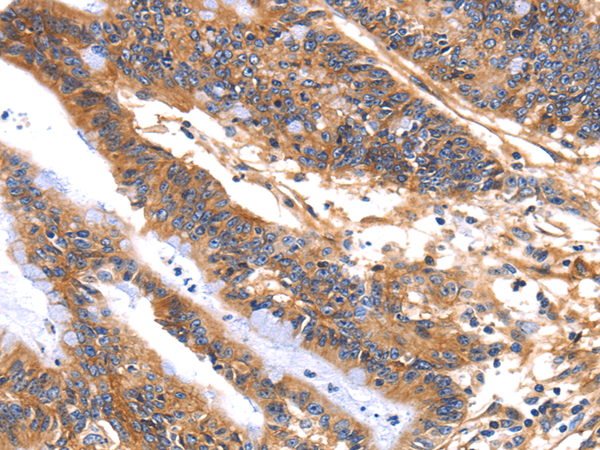

分类: 科研抗体货号: P00473别名: ICSBP; IRF-8; ICSBP1; IMD32A; IMD32B; H-ICSBP应用: IHC反应种属: Human, Mouse